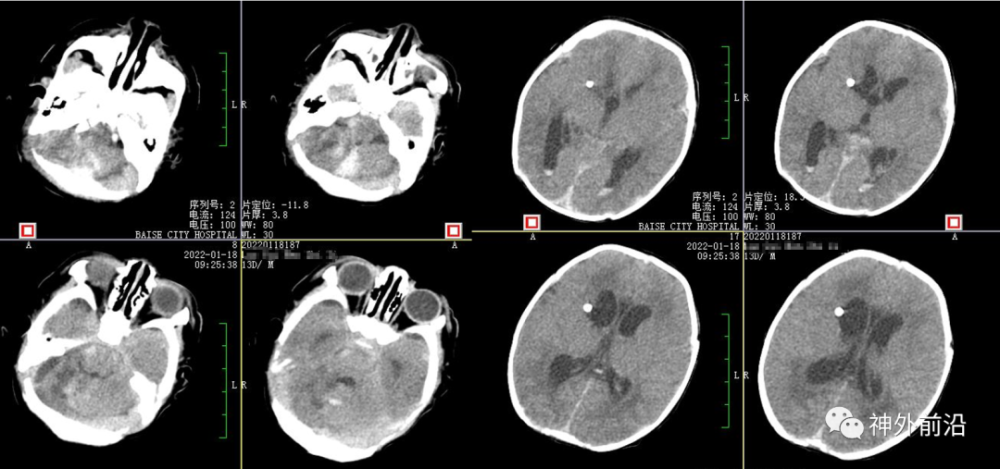

辅助检查:头部CT:两侧小脑半球出血并破入脑室,继发脑室积水。出血量约17ml。

2.术前CT